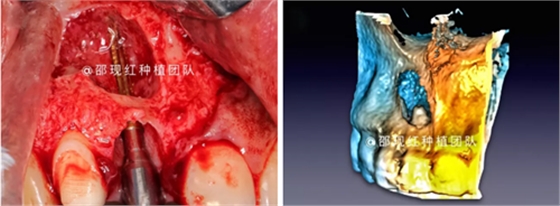

術(shù)中使用科盧森骨粉

「科普篇」你真的了解它嗎?——β-磷酸三鈣

植骨術(shù)后9個月成骨情況